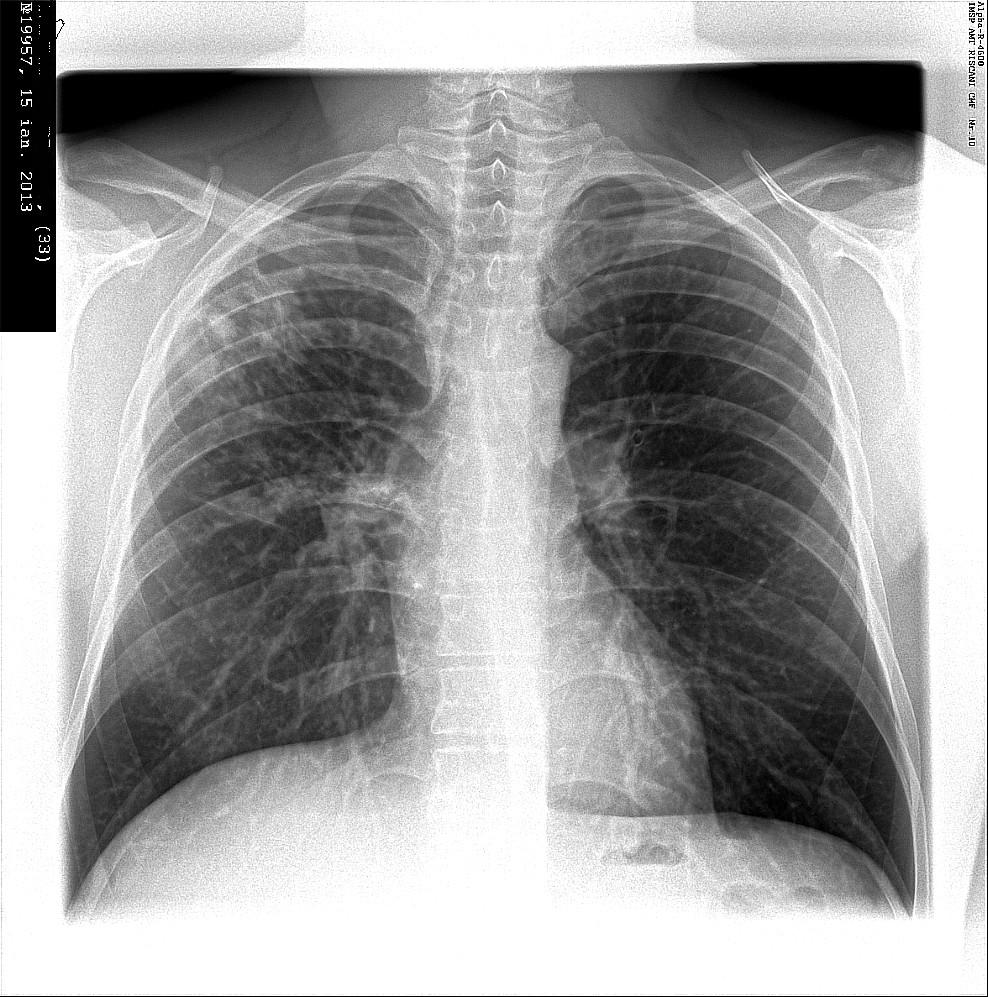

Иллюстрации по теме очагового и инфильтративного туберкулеза